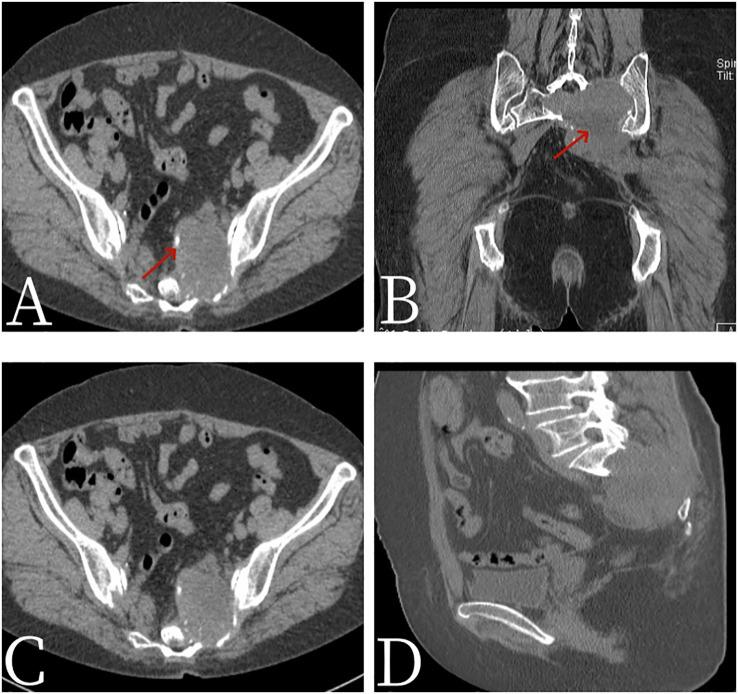

A 67-year-old female patient presented with sacrococcygeal pain without obvious causes on 16 September 2022, with occasional pain at night, as well as aggravated pain during hip flexion and long-distance walking, which could be slightly relieved with rest, without special treatment. For further treatment before 1 month to Jiangxi Provincial People's Hospital, after admission, laboratory tests were negative. Non-contrast CT scan showed expansive bone destruction in the S1-3 vertebrae with soft tissue density of about 58 mm × 46 mm × 52 mm. The boundary was clear, necrosis was visible within the vertebrae, and the boundary between the mass and the anterior sacral blood vessels and rectum was unclear. Non-contrast MRI scan showed mixed signals in lumbosacral masses, with equal signals in T1 and uneven and slightly higher signals in T2. Cystic degeneration and necrosis were visible, with multiple compartments in the lumbosacral masses. MRI enhancement showed uneven enhancement of lumbosacral mass with multiple compartments and no enhanced cystic lesion. The left sacral alar bone is destroyed, as shown by large flaky uneven strengthening. PET/CT showed that S1-3 vertebral body and left sacral alar bone were destroyed and soft tissue shadow formed, invading the sacral canal and the left foramina of S1-3. FDG metabolism was significantly increased, and malignant tumor was diagnosed by PET/CT. Pathological examination: The pathological diagnosis was monophasic PSSS. After systemic chemotherapy and local radiotherapy, no significant signs of recurrence and metastasis were found on CT so far. Follow-up treatment was continued.

2022年9月16日,一名67岁女性患者无明显诱因出现骶尾部疼痛,夜间偶有疼痛,髋关节屈曲及长途行走时疼痛加重,休息后可稍缓解,未进行特殊治疗。1个月前到江西省人民医院进一步诊治,入院后实验室检查均为阴性。非增强CT扫描显示S1-3椎体骨质呈膨胀性破坏,软组织密度影大小约为58 mm×46 mm×52 mm,边界清晰,椎体内可见坏死,肿块与骶前血管及直肠分界不清。非增强MRI扫描显示腰骶部肿块呈混杂信号,T1WI呈等信号,T2WI呈不均匀稍高信号,可见囊变坏死,腰骶部肿块呈多房性。MRI增强扫描显示腰骶部多房性肿块强化不均匀,囊变区无强化。左侧骶骨翼骨质破坏,呈大片状不均匀强化。PET/CT显示S1-3椎体及左侧骶骨翼骨质破坏并形成软组织影,侵犯骶管及左侧S1-3椎间孔,FDG代谢明显增高,PET/CT诊断为恶性肿瘤。病理检查:病理诊断为单相型PSSS。经全身化疗及局部放疗后,目前CT检查未见明显复发及转移征象,继续随访治疗。